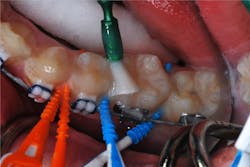

The patient returned for a routine recall appointment on April 6, 2021, wearing fixed orthodontic hardware. A bitewing radiograph was taken (figure 2, top right). The site was cleared with floss, and a new pick soaked with SDF was inserted (figure 3). A small applicator was used to paint sluiceways to enhance the flow of SDF. The pick was slid in and out of the interproximal surfaces a few times (figure 4). The treatment site was immersed in 5% fluoride varnish (figure 5).

There are several brands of dental soft picks available in various sizes. TePe EasyPicks (XS/S-orange and M/L-blue) were used in this case, but other companies market soft picks that can be helpful for this technique (e.g., Sunstar GUM, Practicon Smilegoods PikPak, and others).